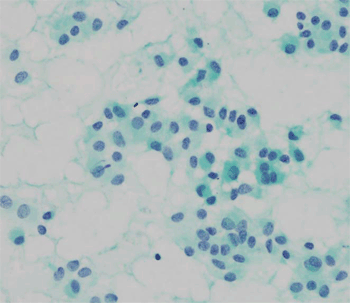

CT 에서 췌장 미부에 내부 낭성 요소를 포함한 비교적 경계가 좋은 9.8 x 7.3 cm 의 종괴가 관찰되었다 (Fig. 1).

Figure 1. A single mass with internal cystic component on pancreas tail